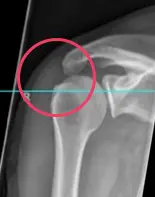

Abbildung: Subacromiales Impingement durch knöchernen Sporn

- Anatomische Enge (z. B. hakenförmiges Acromion, Knochensporne, die den Subacromialraum einengen, Kalkschulter, welche durch die Entzündung des Gewebes zu einer rel. Enge führen)